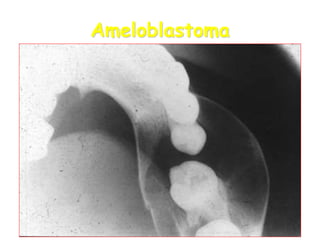

Ameloblastoma

• Ameloblastoma at the

angle of the mandible.

• Expansive form with

oval RL traversed by

few very thin septa

• Soap-like form of

ameloblastoma of the

molar region.

Large multilocular soap bubble appearance.

Typically located in the molar region, angle of the

mandible and ascending ramus

Thin not penetrated cortical plate.

Impacted or neighboring teeth are displaced with

roots often resorped.